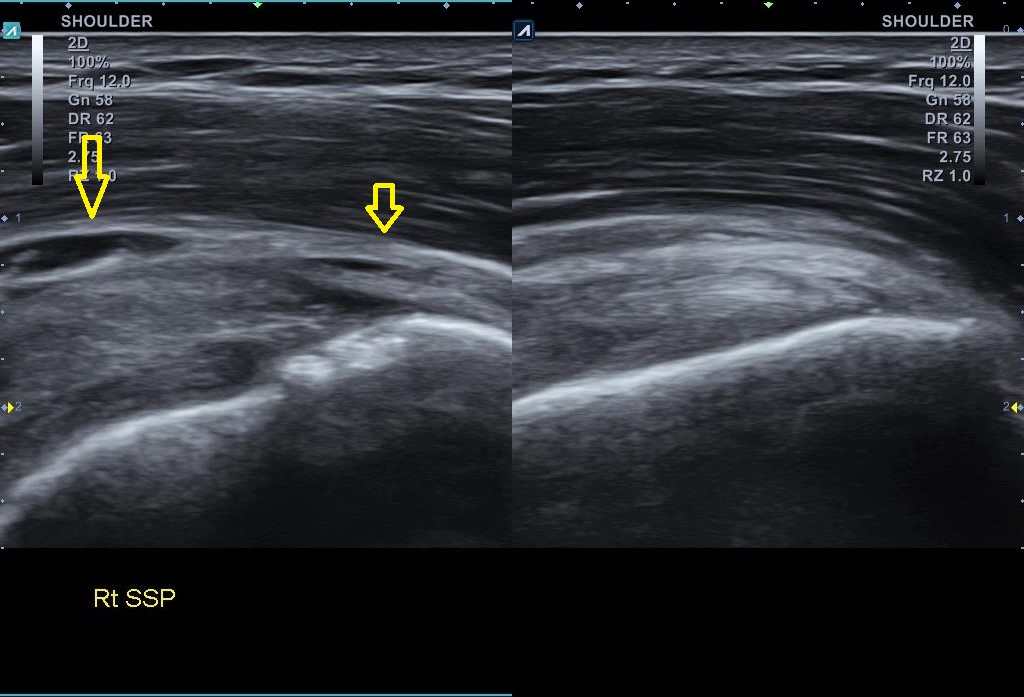

골극이 보이는 상완골 대결절 부위는 극상근 힘줄의 부착부위입니다. x-ray상에 이상 소견이 보인다는건 극상근 힘줄에도 문제가 있을 가능성이 높다는 이야기죠. 힘줄 상태를 확인하기 위해 초음파 검사를 진행했습니다. 결과는...

나 : 초음파 검사 결과를 보니까.... 회전근개 중 극상근이라는 힘줄 파열이네요.

나 : 초음파 검사상 파열 범위와 길이가 아주 심하진 않아서 우선 보존적 치료를 좀 해보고 4주 간격으로 초음파 검사를 몇번 해보면서 지켜봐야 할거 같네요. 지금보다 심해지면 MRI 촬영이 필요할 수 있습니다.